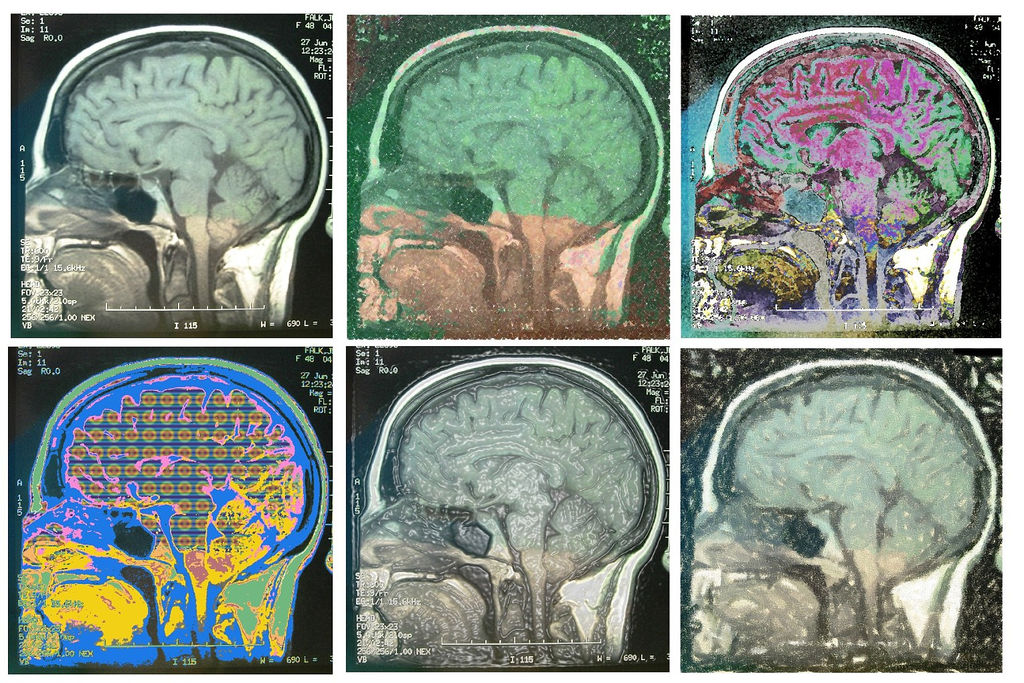

COME INDIVIDUARE un individuo razzista? Da una “fotografia” del suo cervello, sostiene il neuropsicologo dell’università di Ginevra Tobias Brosch. Per “fotografia” si intende una tecnica diagnostica che misura le variazioni di ossigenazione del sangue mentre siamo impegnati nelle più varie attività: la risonanza magnetica funzionale. Questo apparecchio è molto amato dai neuroscienziati perché permette di inferire quali porzioni del cervello sono attive mentre si svolge un determinato compito. E non è meno amato dai media perché permette di pubblicare titoli come “scoperta l’area del razzismo”.

Seguendo questo percorso, Brosch ha mostrato ai suoi volontari delle immagini di individui con colori della pelle differenti e ha osservato quali aree si “accendevano”, identificandole come le zone del cervello che giustificano la propensione al razzismo. “La diversa attività cerebrale – scrive su Psychological Science – registrata nell’osservazione di persone bianche o nere è nettamente più marcata nei soggetti razzisti che non nelle persone senza pregiudizi”. Nata in un laboratorio scientifico, una frase simile può rischiare di finire in tribunale. Un atto di violenza motivata da razzismo – non è escluso che sostenga un giorno un avvocato difensore – può essere causato dalla particolare conformazione del cervello dell’imputato. Alla biologia, dunque, e non al libero arbitrio, può essere imputato un delitto.

La “scoperta dell’area del razzismo” arriva a vent’anni dall’introduzione della risonanza magnetica funzionale per scopi scientifici e coincide con la pubblicazione di un dossier in cui un gruppo di neuropsichiatri che quotidianamente fanno uso di questa tecnica cerca di fare il punto sulla situazione. Tecnica – spiega il rapporto su Perspectives on Psychological Science – che ha permesso di capire meglio come il cervello invecchia, e di cercare una strada per misurare il dolore. Ma a molte altre domande la risonanza magnetica non riesce ancora a dare una risposta.